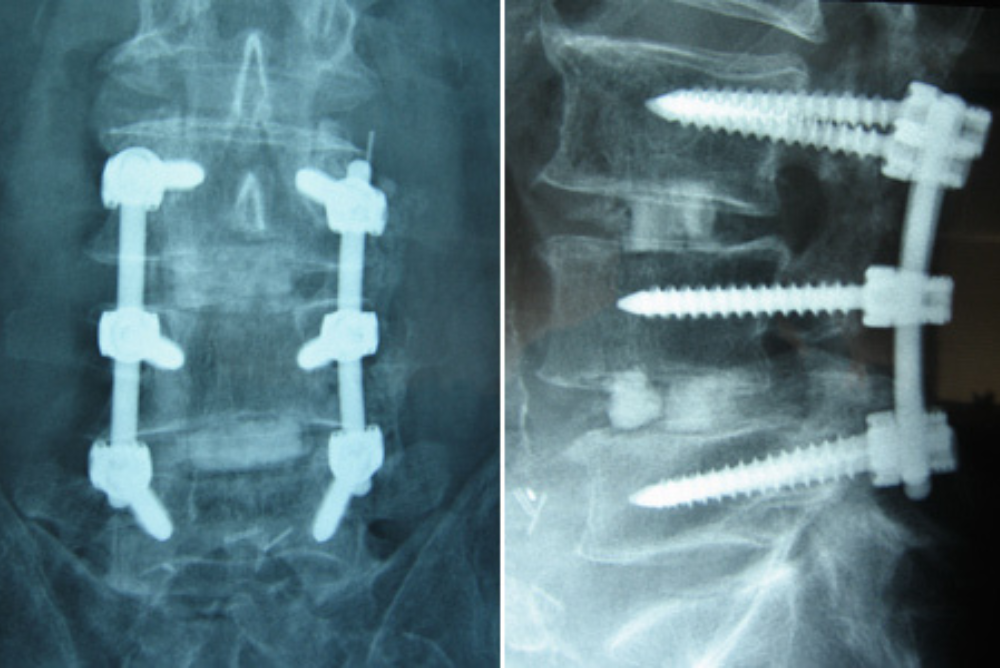

18 May Using the latest medical technology We are always excited to work alongside skilled neurosurgeons like Dr. Shelby Burks, in Miami, Florida, who utilize advanced technologies to help better treat their patients. Here, Dr. Burks performs an L1-3 laminectomy, fusion, and a left-sided L2 partial corpectomy to remove a metastatic sarcoma and stabilize with […]